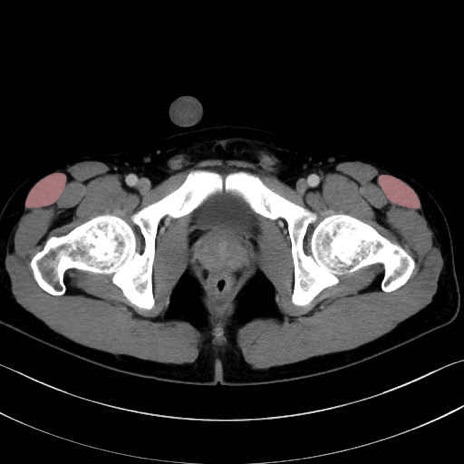

大腿筋膜張筋 (Tensor fasciae latae)